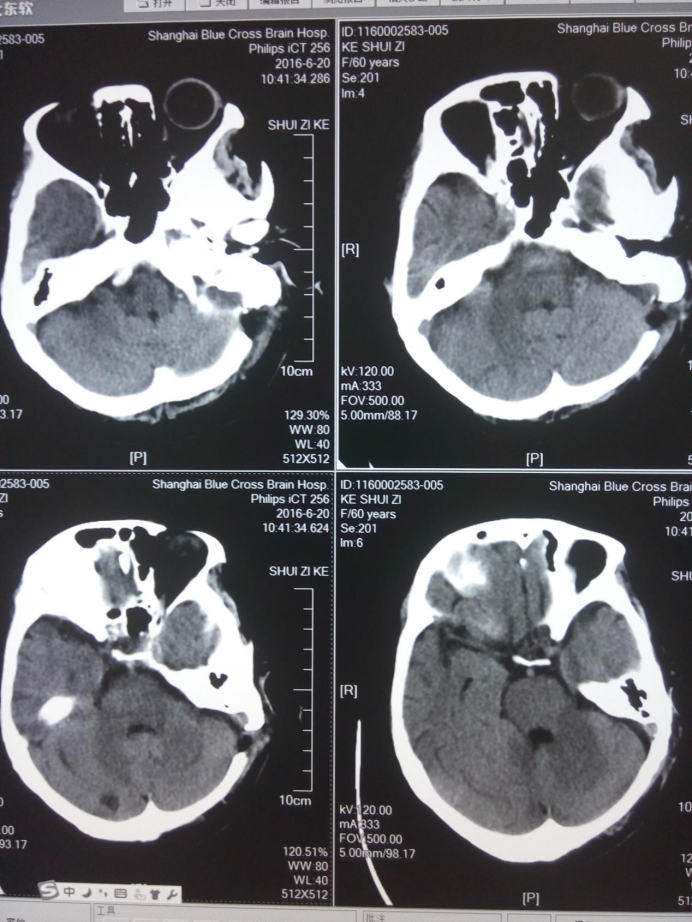

舌咽神經(jīng)微血管減壓術(shù)后頭部CT檢查

手術(shù)治療是治療舌咽神經(jīng)痛優(yōu)先選用的治療方法,術(shù)中所見血管對(duì)迷走神經(jīng)的壓迫較舌咽神經(jīng)更為嚴(yán)重,對(duì)迷走神經(jīng)及舌咽神經(jīng)行充分減壓后患者上述癥狀完全消失。